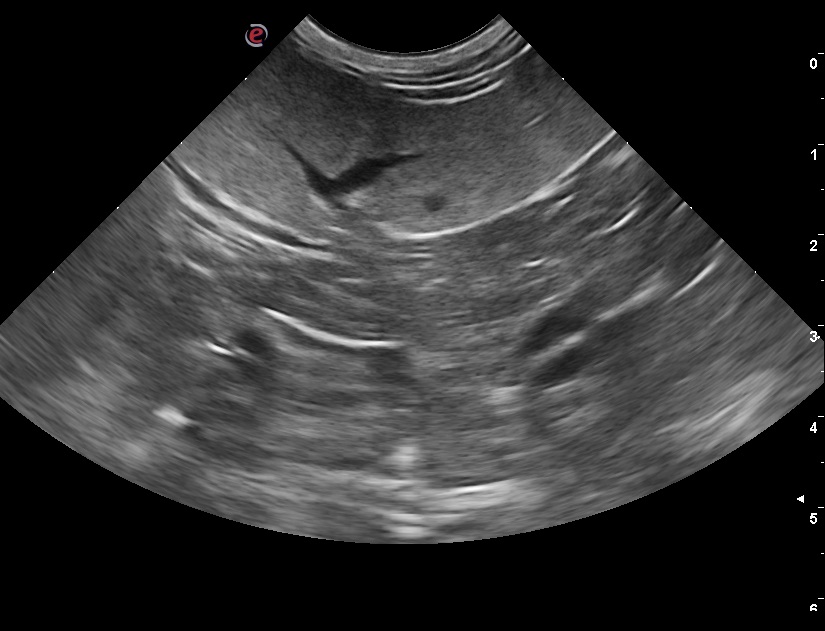

Ecografia

Ecoaddome del cane e del gatto, diagnosi e monitoraggio della gravidanza, centesi endocavitaria, citologia ecoguidata.